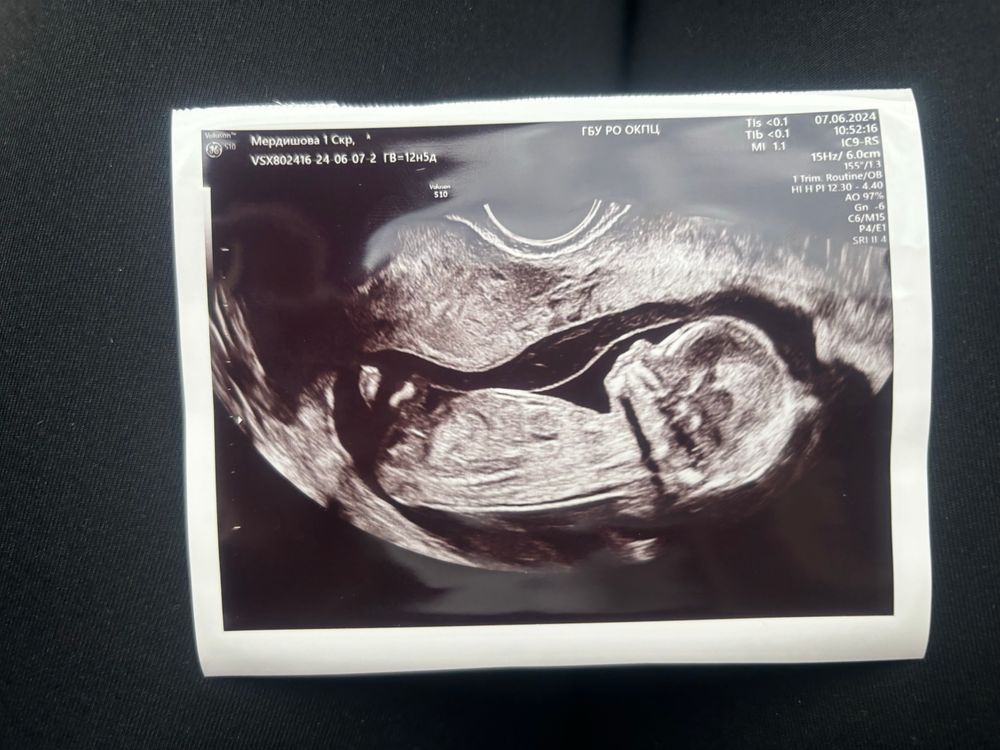

Пол малыша

Вчера только попалось видео про половую «почку» на сроке 12-13 недель Судя по объяснению узи специалиста 90% у вас девочка, на снимке ее видно)

Девочка

Не уверена, но скорее всего девочка)

Судя по чсс мальчик)

Как будто девочка, но я не специалист, поэтому 🤔

Мне почему то кажется,что у вас мальчишка🥰 Как только фото увидела,ещё ничего не читая,в голове сразу "наверное мальчик"☺